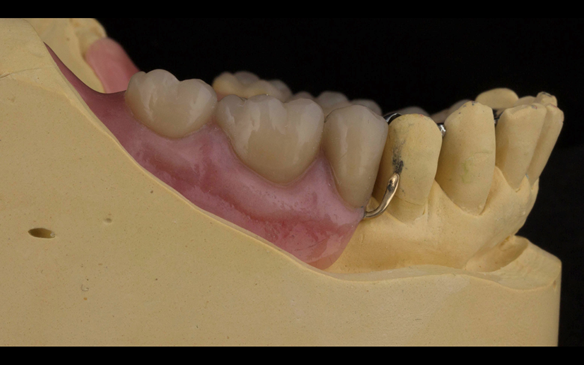

This newsletter describes in step by step detail the transition from acrylic based immediate dentures to metal based definitive dentures.

- Definitive dentures (Mk 2) – complete upper metal reinforced and lower cobalt chromium based partial of hygienic Scandinavian design to be made 9 - 12 months after extractions of all upper teeth and LR5 and LL4